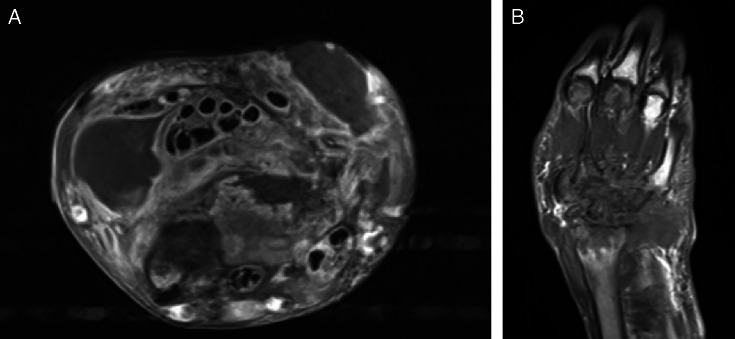

腕部结核分枝杆菌(TB)复合骨髓炎十分罕见,而多菌性结核骨髓炎则更为罕见。作者描述了一例不寻常的多菌性结核腕骨髓炎病例。病例患者的手腕上有两个隐匿生长的结节,病史长达 2.5 年。他接受了清创术,组织培养出了耐甲氧西林金黄色葡萄球菌、粪肠球菌,后来又发现了结核复合菌。他开始服用万古霉素、利福平、异烟肼、吡嗪酰胺和乙胺丁醇,症状有所改善。该病例强调了对骨髓炎的非典型表现进行广泛鉴别和全面检查的重要性。不常见病因的诊断对于明确治疗至关重要。

Wrist Mycobacterium tuberculosis (TB) complex osteomyelitis is rare, with polymicrobial TB osteomyelitis even more uncommon. The authors describe an unusual case of polymicrobial TB wrist osteomyelitis. The case patient presented with a 2.5-year history of 2 insidiously growing nodules on his wrist. He underwent debridement, and tissue cultures grew methicillin-resistant Staphylococcus aureus, Enterococcus faecalis, and, later, TB complex. He was started on vancomycin, rifampin, isoniazid, pyrazinamide, and ethambutol with improvement in symptoms. This case emphasizes the importance of a broad differential and thorough workup for atypical presentations of osteomyelitis. Diagnosis of uncommon etiologies is essential for definitive treatment.